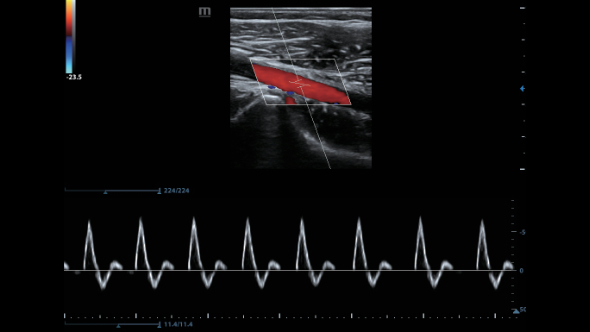

–ü―Ä–Β–¥–Ϋ–Α–Ζ–Ϋ–Α―΅–Β–Ϋ–Η–Β DC-80 EXP ―¹–Ψ―¹―²–Ψ–Η―² –≤ ―²–Ψ–Φ, ―΅―²–Ψ–±―΄ –Ω–Ψ–Φ–Ψ–≥–Α―²―¨ –£–Α–Φ ―¹–Ω–Ψ–Κ–Ψ–Ι–Ϋ–Ψ ―Ä–Β–Α–≥–Η―Ä–Ψ–≤–Α―²―¨ –Ϋ–Α ―É―¹–Μ–Ψ–Ε–Ϋ―è―é―â–Η–Β―¹―è –¥–Β–Ϋ―¨ –Ψ―²–Ψ –¥–Ϋ―è –Κ–Μ–Η–Ϋ–Η―΅–Β―¹–Κ–Η–Β –Ζ–Α–¥–Α―΅–Η, –Ω―Ä–Β–¥–Ψ―¹―²–Α–≤–Μ―è―è –Ω―Ä–Β–≤–Ψ―¹―Ö–Ψ–¥–Ϋ–Ψ–Β –Κ–Α―΅–Β―¹―²–≤–Ψ –≤–Η–Ζ―É–Α–Μ–Η–Ζ–Α―Ü–Η–Η, –Ω–Β―Ä–≤–Ψ–Κ–Μ–Α―¹―¹–Ϋ―΄–Β –Η–Ϋ―²–Β–Μ–Μ–Β–Κ―²―É–Α–Μ―¨–Ϋ―΄–Β ―Ä–Β―à–Β–Ϋ–Η―è –Η –Φ–Ϋ–Ψ–≥–Ψ–Β –¥―Ä―É–≥–Ψ–Β βÄΠ

–£–Ϋ–Β–¥―Ä–Β–Ϋ–Η–Β –≤ DC-80 EXP –¥–Α―²―΅–Η–Κ–Ψ–≤ ―¹–≤–Β―Ä―Ö–≤―΄―¹–Ψ–Κ–Ψ–Ι –Ω―Ä–Ψ–Η–Ζ–≤–Ψ–¥–Η―²–Β–Μ―¨–Ϋ–Ψ―¹―²–Η –Ψ–±–Β―¹–Ω–Β―΅–Η–≤–Α–Β―² –¥–Μ―è –£–Α―¹ –Ω―Ä–Β–≤–Ψ―¹―Ö–Ψ–¥–Ϋ–Ψ–Β –Κ–Α―΅–Β―¹―²–≤–Ψ –≤–Η–Ζ―É–Α–Μ–Η–Ζ–Α―Ü–Η–Η.

–ë–Μ–Α–≥–Ψ–¥–Α―Ä―è ―¹–Ψ―΅–Β―²–Α–Ϋ–Η―é ―²–Β―Ö–Ϋ–Ψ–Μ–Ψ–≥–Η–Η 3–Δ? (–Δ―Ä–Ψ–Ι–Ϋ–Ψ–Ι ―¹–Ψ–≥–Μ–Α―¹―É―é―â–Η–Ι ―¹–Μ–Ψ–Ι, ―²–Β―Ö–Ϋ–Ψ–Μ–Ψ–≥–Η―è –Ω–Ψ–Μ–Ϋ–Ψ―¹―²―¨―é ―Ä–Α–Ζ–¥–Β–Μ–Β–Ϋ–Ϋ―΄―Ö –Κ―Ä–Η―¹―²–Α–Μ–Μ–Ψ–≤, ―²–Β―Ä–Φ–Ψ–Κ–Ψ–Ϋ―²―Ä–Ψ–Μ―¨ –Α–Κ―É―¹―²–Η―΅–Β―¹–Κ–Ψ–Ι –Μ–Η–Ϋ–Ζ―΄) –Η –Φ–Ψ–Ϋ–Ψ–Κ―Ä–Η―¹―²–Α–Μ–Μ–Η―΅–Β―¹–Κ–Η―Ö –¥–Α―²―΅–Η–Κ–Ψ–≤ –Ψ–±–Β―¹–Ω–Β―΅–Η–≤–Α–Β―²―¹―è –Κ–Α–Κ –±–Ψ–Μ–Β–Β –≤―΄―¹–Ψ–Κ–Α―è ―Ä–Α–Ζ―Ä–Β―à–Α―é―â–Α―è, ―²–Α–Κ –Η –Ω―Ä–Ψ–Ϋ–Η–Κ–Α―é―â–Α―è ―¹–Ω–Ψ―¹–Ψ–±–Ϋ–Ψ―¹―²―¨, –≤ ―Ä–Β–Ζ―É–Μ―¨―²–Α―²–Β ―΅–Β–≥–Ψ ―Ä–Β―à–Α–Β―²―¹―è –Ω―Ä–Ψ–±–Μ–Β–Φ–Α –Η―¹―¹–Μ–Β–¥–Ψ–≤–Α–Ϋ–Η–Ι ―²–Β―Ö–Ϋ–Η―΅–Β―¹–Κ–Η ―¹–Μ–Ψ–Ε–Ϋ―΄―Ö –Ω–Α―Ü–Η–Β–Ϋ―²–Ψ–≤.

–Θ–Μ―¨―²―Ä–Α–Μ–Β–≥–Κ–Η–Ι –Η –≤―΄―¹–Ψ–Κ–Ψ–Ω–Μ–Ψ―²–Ϋ―΄–Ι –Ψ–±―ä–Β–Φ–Ϋ―΄–Ι –¥–Α―²―΅–Η–Κ –Ψ–±–Β―¹–Ω–Β―΅–Η–≤–Α–Β―² –Ω―Ä–Β–≤–Ψ―¹―Ö–Ψ–¥–Ϋ–Ψ–Β –Κ–Α―΅–Β―¹―²–≤–Ψ –≤–Η–Ζ―É–Α–Μ–Η–Ζ–Α―Ü–Η–Η –≤ –Α–Κ―É―à–Β―Ä―¹―²–≤–Β –≤ ―Ä–Β–Ε–Η–Φ–Α―Ö 2D, –Π–î–ö, 3D/4D –¥–Μ―è –±–Ψ–Μ―¨―à–Β–Ι –¥–Η–Α–≥–Ϋ–Ψ―¹―²–Η―΅–Β―¹–Κ–Ψ–Ι ―É–≤–Β―Ä–Β–Ϋ–Ϋ–Ψ―¹―²–Η –Η –Ω–Ψ–≤―΄―à–Β–Ϋ–Η―è –Κ–Α―΅–Β―¹―²–≤–Α –Η―¹―¹–Μ–Β–¥–Ψ–≤–Α–Ϋ–Η―è;